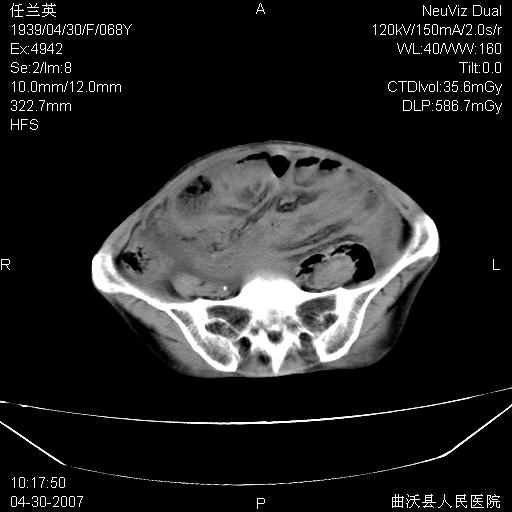

患者,女,68岁,感觉腹部憋涨发硬数天,查b超发现左盆腔有囊性肿物和少量腹水,行ct检查

1.考虑卵巢肿瘤并腹腔广泛性转移可能性大;

2.腹盆腔少量积液。

支持左侧卵巢恶性肿瘤伴网膜、腹膜广泛转移。

支持:左侧卵巢恶性肿瘤伴网膜、腹膜 腹膜后(淋巴结)广泛转移。

网膜、腹膜广泛转移考虑来源于左侧卵巢癌可能性大。不除外来源于消化系的肿瘤。

支持卵巢恶性肿瘤腹膜.肠系膜.淋巴结转移,

难的一见 典型 - 网膜饼  冰冻骨盆 可以当教学片了